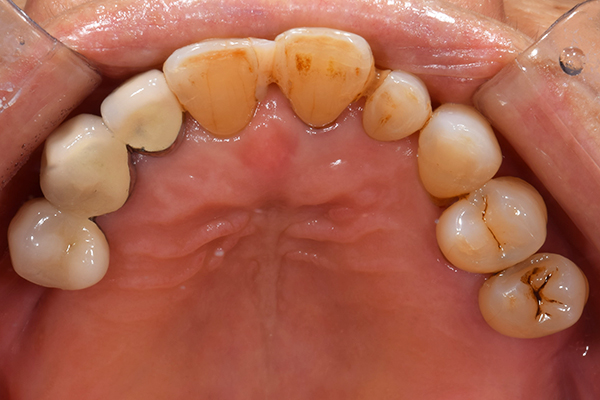

上下の入れ歯が外れやすくなったということでいらっしゃいました。 顎の骨はしっかりしていましたので、精密な型取りさえすればしっかりした入れ歯がつくれると思いました。 また下には6本歯が残っていましたが、虫歯になっている歯もありました。 かぶせ物のなかで大きな虫歯があった歯があり、1本だけ残せない状態でした。

上の入れ歯は確かに吸着は甘くなっていました。 また下の入れ歯はバネの一部が壊れており、安定感がなくなっていました。

精密な型取りの後、噛み合わせのチェックをしていきました。 かぶせ物も同時に作っていきました。

歯を並べた後、かぶせ物のフレーム作ってもらいました。先に歯を並べて理想の位置を決めておくことが大切です。

完成した入れ歯とかぶせ物です。 入れ歯への寛容度が高い患者様でしたので、 金属は使用せず、プラスチックのみで上は仕上げました。 下顎も歯は1本減ってしまいましたが、しっかり 入れ歯が維持できる様な構造にしました。

お口の中に入れた状態です。 見た目も最初とほとんど変わることなく作成できました。 維持や吸着に関しても問題ないようでした。